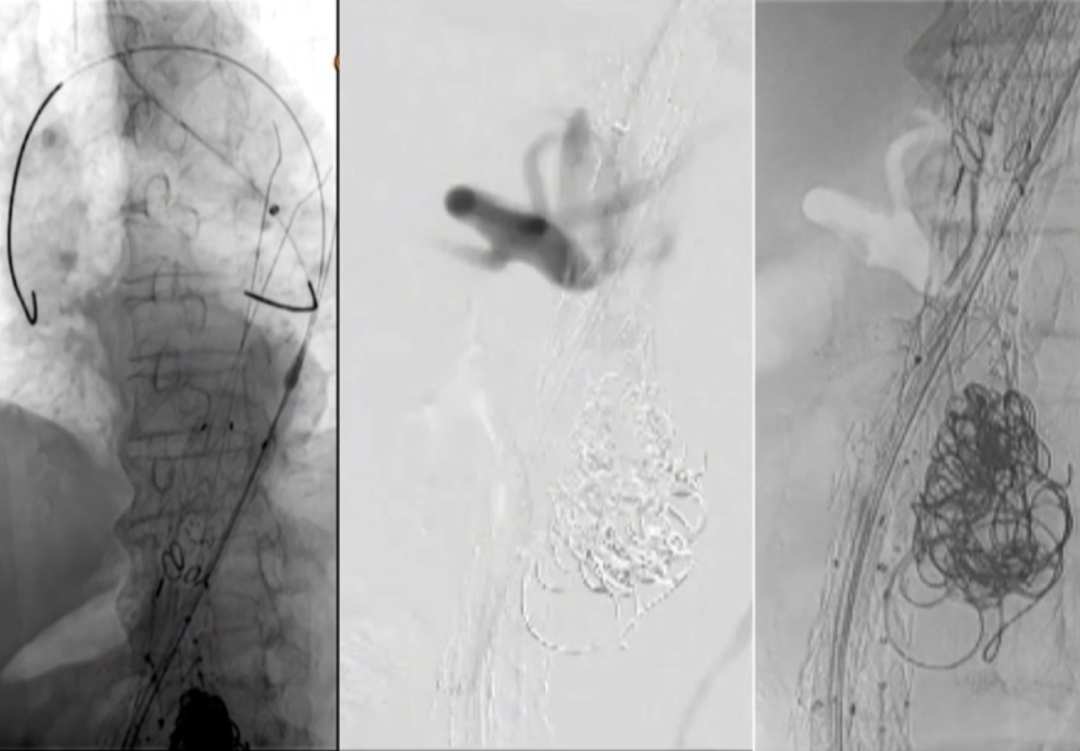

超选SMA,桥接8-100mm Viabahn,内衬8-60mm Absolute裸支架

超选CA,桥接8-100mm Viabahn

超选RRA烟囱支架,桥接6-100mm+6-50mm Viabahn

超选LRA烟囱支架,桥接6-100mm Viabahn

右侧:16-16-140mm Excluder髂腿;

左侧:16-16-120mm Excluder髂腿

术后造影